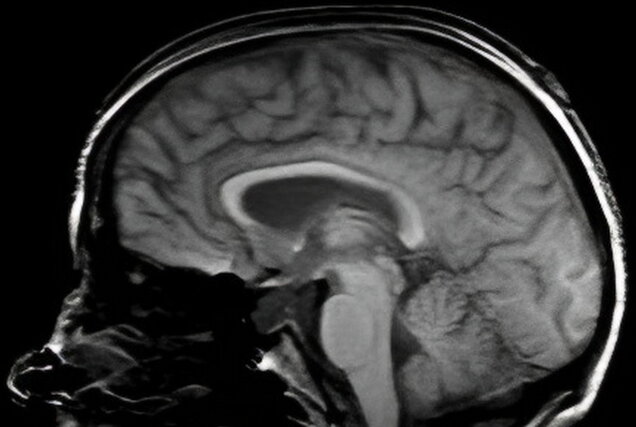

Subarachnoid hemorrhage scan

The Life-Altering Day: My Subarachnoid Hemorrhage

Category Medical Author Denise Milward Date 04/03/2026 Read time 4:30

My journey through a life-altering experience with a subarachnoid hemorrhage.